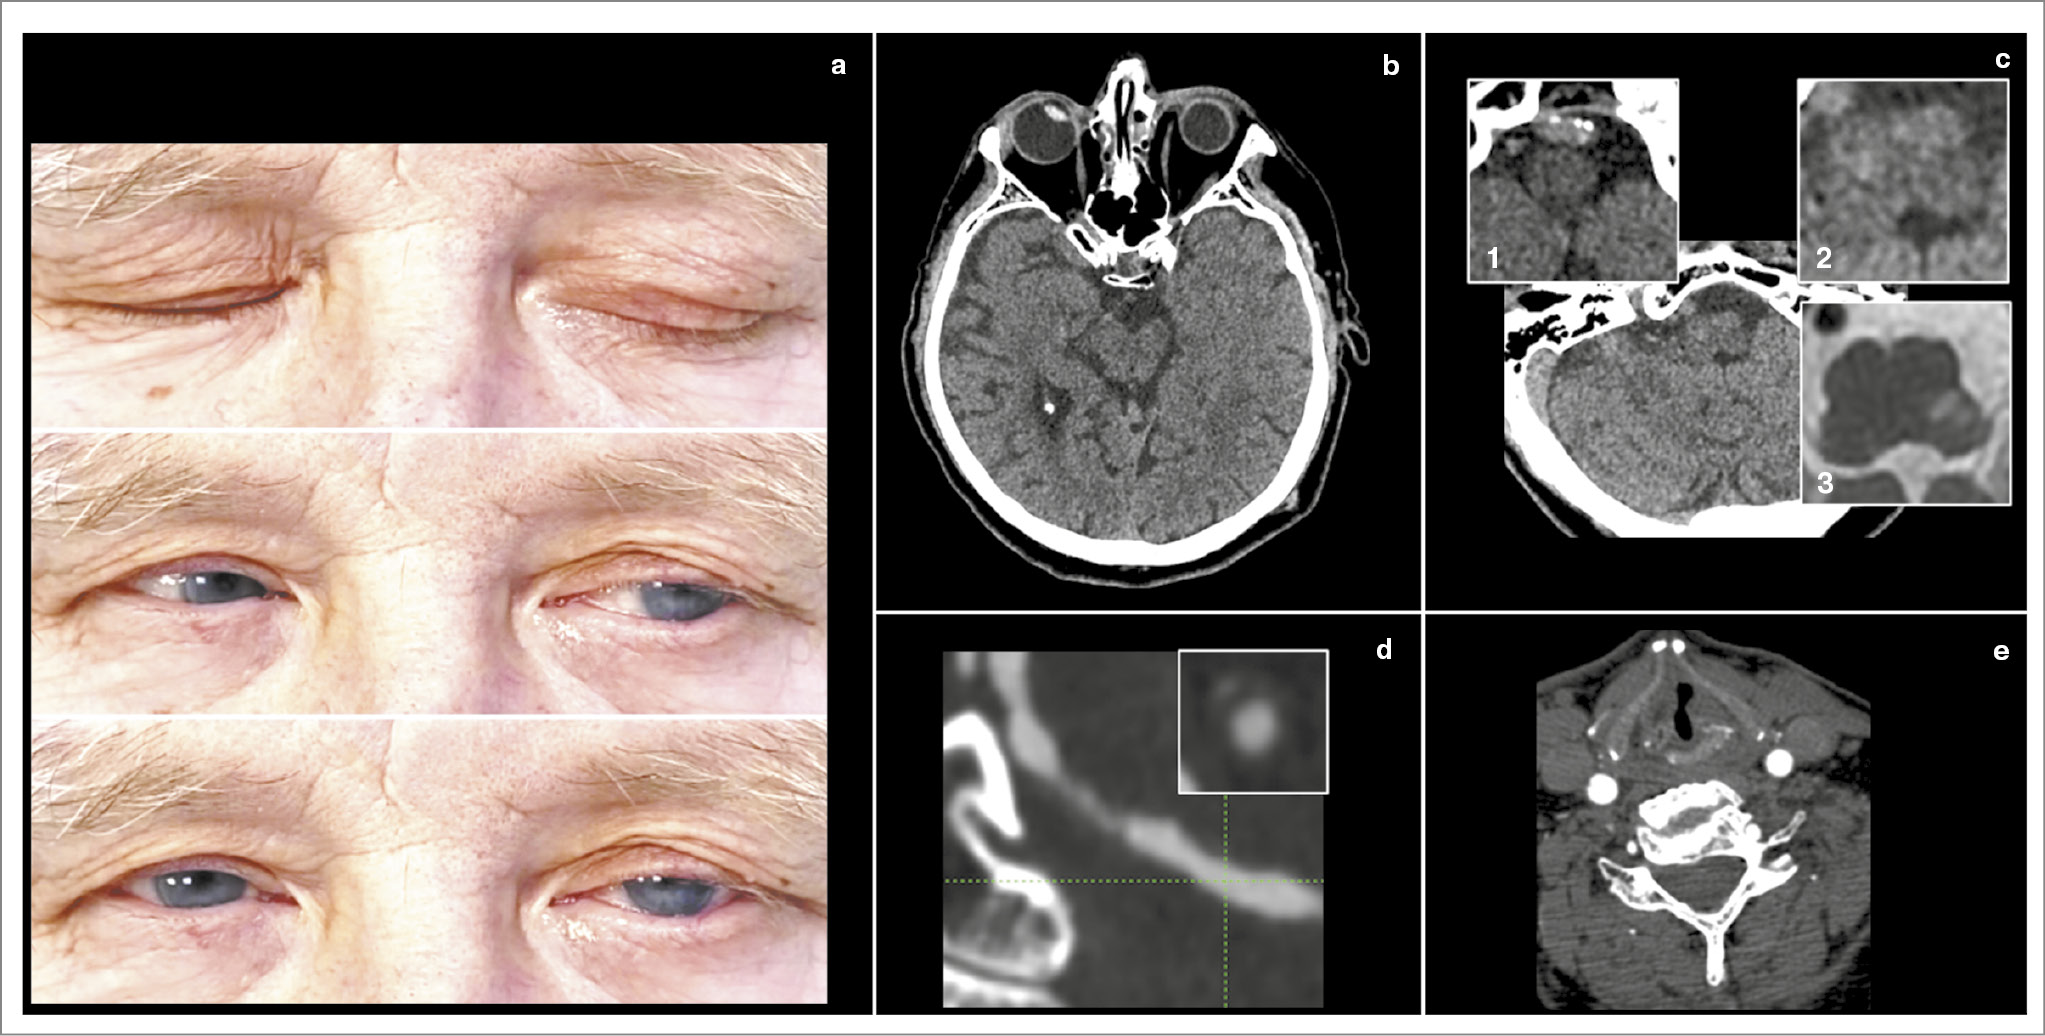

Синдром Горнера. Оценивая синдром Горнера, важно помнить, что при ярком свете парасимпатический тонус минимален, а симпатический – максимален, поэтому анизокория может быть незаметна. В темноте зрачок расширяется за счет релаксации сфинктера (пассивно), медленно, что приводит к возникновению феномена dilation lag (задержка расширения зрачка); рис. 4 [31]. Наряду с ипсилатеральной атаксией и контралатеральной гипестезией синдром Горнера входит в клиническую триаду ЛМИ, предложенную R. Sacco и соавт. [5].

Рис. 4. Динамическая анизокория при синдроме Горнера у пациента с ЛМИ. При помощи видеоочков Френзеля продемонстрирован феномен задержки расширения зрачка при резком переходе из яркого света в полную темноту у пациента с ЛМИ (a, МРТ ДВИ) вследствие хронической окклюзии сегмента IV правой позвоночной артерии (c – КТА, окклюзия указана звездочкой).